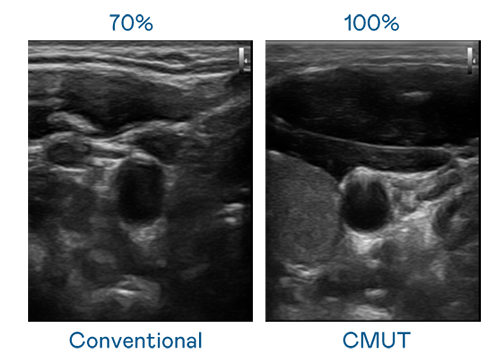

CMUT 技术是一种用电容式微机电元件来产生超音波讯号的技术。与传统 PZT 压电式技术相比,CMUT 频宽增加 30%,更宽频的超音波讯号让影像解析度大幅提升,是实现高影像品质医疗超音波扫描、促进精准医疗发展的关键技术。

超音波影像的解析度高低,首先取决于探头能发出的讯号频宽。抖圈 CMUT 可提供高清晰的超音波讯号,提供高频宽、高灵敏度、影像纹理细节更高的超音波影像,协助医护人员缩短影像判读时间及利用精准的医疗影像进行诊断。